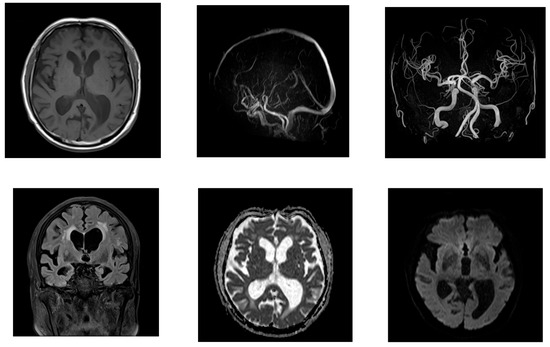

2.2. Case 2